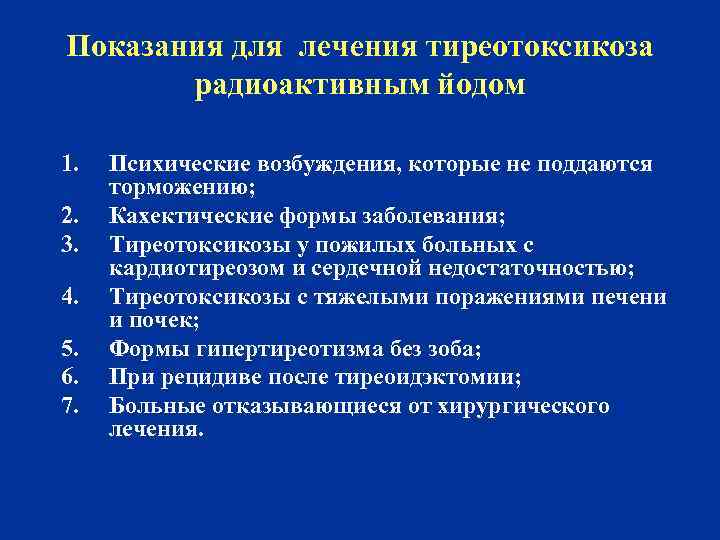

Показания для лечения тиреотоксикоза радиоактивным йодом 1. 2. 3. 4. 5. 6. 7. Психические возбуждения, которые не поддаются торможению; Кахектические формы заболевания; Тиреотоксикозы у пожилых больных с кардиотиреозом и сердечной недостаточностью; Тиреотоксикозы с тяжелыми поражениями печени и почек; Формы гипертиреотизма без зоба; При рецидиве после тиреоидэктомии; Больные отказывающиеся от хирургического лечения.

Показания для лечения тиреотоксикоза радиоактивным йодом 1. 2. 3. 4. 5. 6. 7. Психические возбуждения, которые не поддаются торможению; Кахектические формы заболевания; Тиреотоксикозы у пожилых больных с кардиотиреозом и сердечной недостаточностью; Тиреотоксикозы с тяжелыми поражениями печени и почек; Формы гипертиреотизма без зоба; При рецидиве после тиреоидэктомии; Больные отказывающиеся от хирургического лечения.